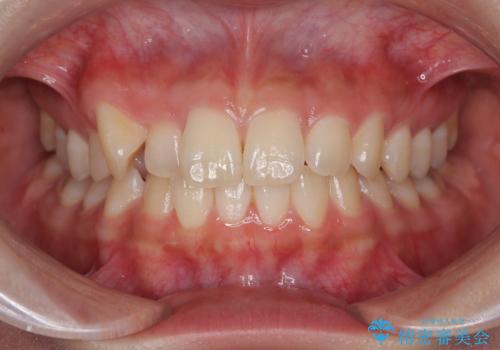

外に飛び出して磨きにくい奥歯と上下前歯の隙間 インビザラインによる矯正治療

- 上下前歯の隙間と、外側を向いていて歯磨きのしにくい奥歯を気にして来院された患者様です。

下顎前歯が1本欠損しており、上下アーチはアンバランスとなりますが、インビザラインを用いて上下の隙間を改善しながら歯列を整えることとしました。

下顎前歯の1本欠損により左右の咬合が不安定となり、治療経過で噛みにくい状態が続きましたが、最終的には違和感なく噛めるようになりました。